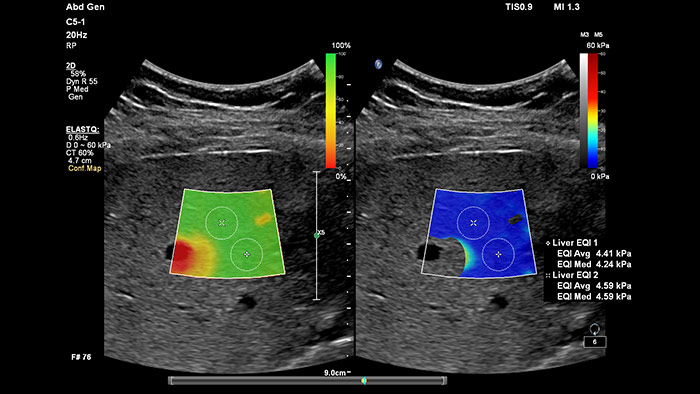

A elastografia por ondas transversais ecográficas proporciona um método não invasivo, reprodutível e de fácil aplicação para a avaliação da rigidez dos tecidos. Investigações sugerem que, em vez de um procedimento de biópsia dispendioso e doloroso, uma simples ultrassom com elastografia por ondas transversais pode tornar-se rotina na avaliação do estado de doenças hepáticas. A elastografia por ondas transversais de alto desempenho do ElastQ Imaging inclui a avaliação quantitativa codificada por cores através de regiões de interesse (ROI) em tempo real e de grandes dimensões da rigidez do tecido. O ElastQ Imaging também inclui a capacidade de efetuar medições retrospetivas nas imagens armazenadas e uma apresentação de mapa de confiança única utiliza a análise inteligente para acrescentar uma garantia adicional de que as medições do utilizador são obtidas em áreas de tecido com propagação adequada de ondas transversais.

A medição da rigidez do fígado é efetuada em segundos através de um simples exame não invasivo.